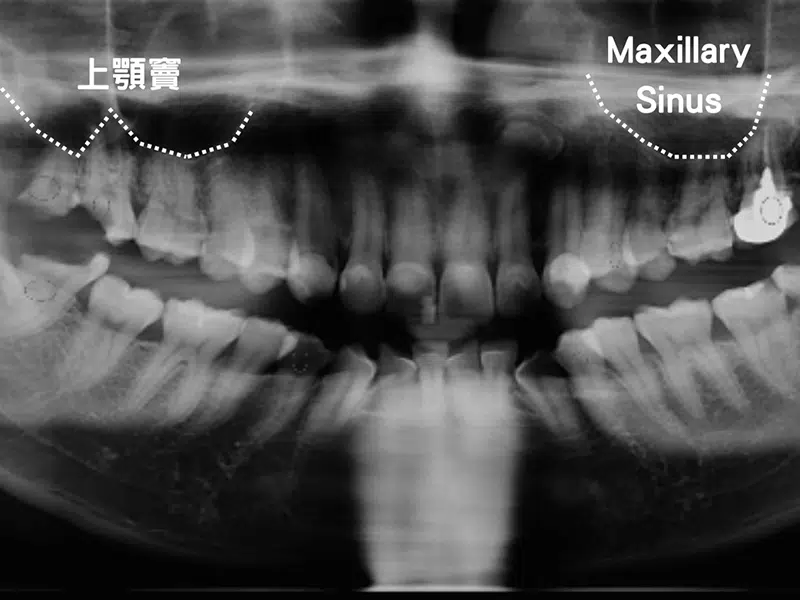

植牙是鈦金屬構成的人工牙根,種入齒槽骨後和骨頭產生骨整合便可開始承受咀嚼的力量。不論是植牙還是自然牙,牙醫師都希望牙根的周圍有足夠的軟硬組織提供保護來避免牙菌斑、刷牙過度、硬質食物摩擦的傷害。當你因為牙周病或是缺牙過久造成骨頭流失,我們希望在植牙前能回復原本的軟硬組織豐隆度,這時候就需要補骨跟補皮。

這是一位上顎前牙植牙的患者,側門牙因為牙周病的關係,軟硬組織都萎縮比較嚴重,可以發現頰側是往內凹的。由於骨頭的量不夠,所以植牙手術時植入的人工牙根是外露的,為了保護人工牙根所以要在上面放上骨粉與再生膜再進行縫合。